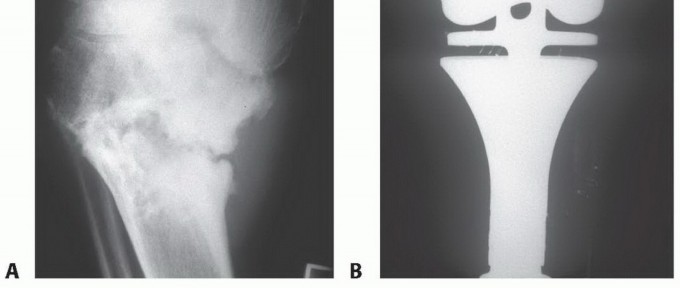

* الكشط والعلاج المساعد (Curettage and Adjuvant Therapy): تُستخدم عادة لأورام العظام الحميدة، حيث يتم كشط الورم من داخل العظم، ثم يتم استخدام مواد مساعدة مثل الفينول أو النيتروجين السائل أو الكي الكهربائي لتدمير أي خلايا ورمية متبقية.

يُعد العلاج بالتبريد، خاصةً بتقنية الصب المباشر بالنيتروجين السائل، ثورة حقيقية في علاج أورام العظام، حيث يقدم بديلاً فعالاً وآمنًا للجراحات الكبرى، مع الحفاظ على الطرف المصاب ووظيفته. يعتمد هذا النهج على تدمير الخلايا السرطانية عن طريق تعريضها لدرجات حرارة منخفضة جدًا، مما يؤدي إلى تجميدها وموتها.

تقنية الصب المباشر بالنيتروجين السائل تفاصيل الإجراء

تعتبر تقنية الصب المباشر بالنيتروجين السائل (Direct Pouring Liquid Nitrogen Technique) في العلاج بالتبريد لأورام العظام من التقنيات المتقدمة التي تتطلب دقة عالية وخبرة جراحية متخصصة. يفضل الأستاذ الدكتور محمد هطيف هذه التقنية نظرًا لفعاليتها في تحقيق تجميد عميق وشامل للورم، مع الحفاظ على الأنسجة السليمة المحيطة.